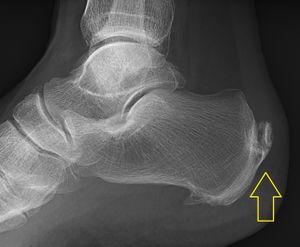

Calcification deposits forming an enthesophyte within the Achilles tendon at its calcaneal insertion. The Achilles tendon is wider than normal, further suggesting inflammation.